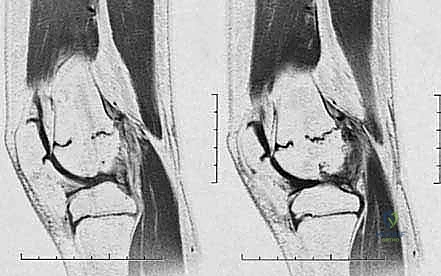

2. التصوير بالرنين المغناطيسي (MRI)

هو المعيار الذهبي (Gold Standard) اليوم. الرنين المغناطيسي يوفر رؤية مباشرة لغضروف صفيحة النمو (الذي لا يظهر في الأشعة السينية). من خلال الـ MRI، يستطيع الدكتور هطيف رسم خريطة دقيقة (Mapping) للعائق العظمي: أين يقع بالضبط؟ وما هي مساحته بالنسبة للمساحة الكلية لصفيحة النمو؟

| الرنين المغناطيسي (MRI) | المعيار الذهبي. يظهر الغضروف، بدون إشعاع، رسم خريطة ثلاثية الأبعاد (Mapping). | تكلفة أعلى، قد يحتاج الطفل الصغير للتخدير ليبقى ثابتاً. | التقييم النهائي قبل الجراحة لتحديد حجم وموقع العائق. |